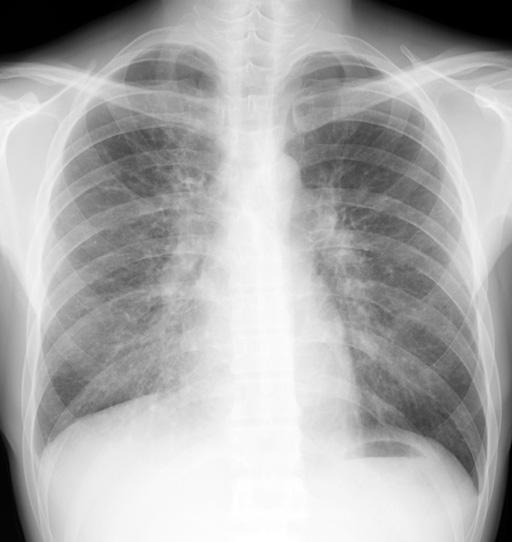

胸部単純X線写真

・両側肺門部陰影の拡大

・両側中下肺野優位に 肺門部を中心とした 肺紋理増強、小粒状影